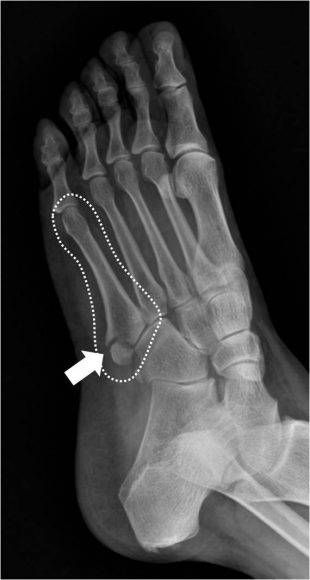

중족골은 발목뼈와 발가락뼈를 잇는 5개의 뼈로 이루어져 있는데 흔히 발등뼈로도 부른다. 중족골 골절은 5개 뼈 중 몇 번째 뼈가 골절되느냐에 따라 앞에 숫자가 붙는다. 그중에서도 제5중족골은 새끼발가락 쪽 뼈가 골절된 상태로 치료가 유독 까다롭다. 제5중족골을 세 구역(제1구역·제2구역·제3구역)으로 나눠 어느 부위가 골절됐는지에 따라 치료방법과 예후가 다르기 때문이다.

제1구역에 발생하는 견열 골절의 경우 전위가 심하거나 관절면 침범이 30% 이상인 경우 수술이 필요한 것으로 알려져 있으나 통깁스로 보존적 치료를 하기도 한다. 환자 입장에서 깁스는 땀이 차고 간지럽고 쉽게 벗지 못하는 불편함이 있어 이러한 깁스 치료 대신 간편한 의료용 신발(Hard-Soled Shoe)을 이용하면 훨씬 가볍고 편리하다.

의료용 신발의 원리는 통깁스와 동일하다. 골절 부위가 잘 유합되려면 골절 부위를 고정하는 것이 필요한데 통깁스가 이런 역할을 해준다. 다만 제5중족골 기저부 견열 골절의 경우 의료용 신발만으로도 고정 가능하고 발목까지 고정하는 통깁스보다 발 부위만 고정해도 충분하기 때문에 의료용 신발로도 치료가 가능하다.

연구는 제5중족골 기저부 견열 골절 치료를 위해 의료용 신발과 통깁스 치료의 통증 점수와 치료 유무를 비교·확인하기 위해 진행됐다. 김형년 교수 연구팀은 골절 6개월 후 통깁스를 한 환자군(50명)과 딱딱한 의료용 신발을 착용한 환자군(46명)의 통증을 비교했다. 연구 결과, 깁스로 치료한 경우와 의료용 신발로 치료한 경우 골절 후 6개월에 측정한 통증 점수에 큰 차이가 없었으며 두 경우 모두 불유합 없이 잘 치료됐다.